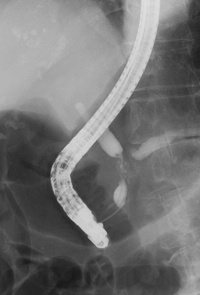

X線透視検査は、よく知られている胃のバリウム検査はじめ、食道、小腸、大腸といった消化管の癌の診断に用いられています。当院の透視装置は平面検出器(FPD: Flat Panel Detector)搭載X線TV装置であり、このFPD装置で撮影された画像は、直接、画像支援システムに送信され、各診療科で鮮明な画像を見ることが可能となりました。他に、電子内視鏡装置を併用して胆道・膵管を造影する内視鏡的逆行性胆道膵管造影(ERCP: Endoscopic Retrograde Cholangio-Pancreatography)も行っており、膵・胆道系の癌の診断に役立っています。閉塞性黄疸に対しては、ステント留置術も行っています。

| 膵癌に対する胆道ステント留置術 | |